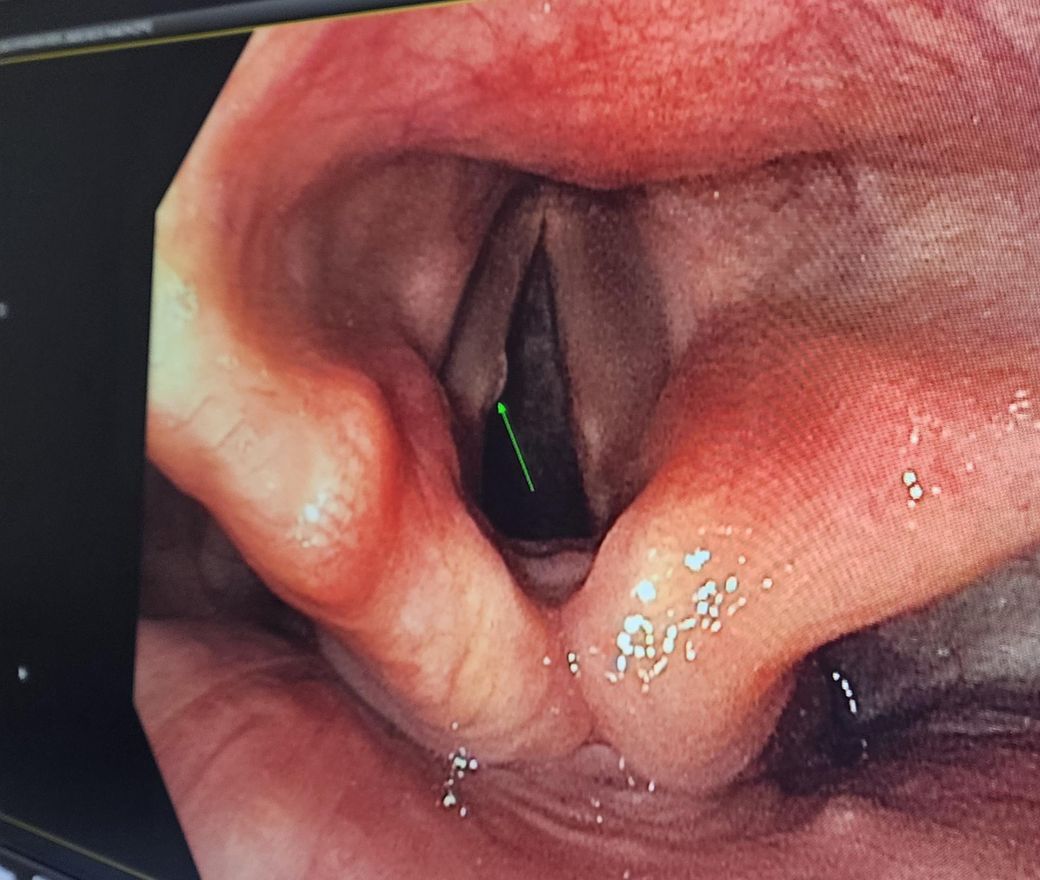

위내시경 검사에서 성대? 입구에 저렇게 있는데 가래인지 결절인지 모르겠고

• 1번 째 사진

올려주신 사진상 성대 결절과 유사한 병변이 관찰되지만 이비인후과에서 시행한 후두경 검사에서 특이 소견이 없었다면 실제 병변 가능성은 낮습니다. 상부 위장과 내시경을 시행하는 과정에서 내시경을 삽입하면서 후두부를 일부 관찰하지만 이 부위에서 내시경이 오래 머무를 경우 구역 반사에 의한 구역질이 유발되므로 인후두를의정확한 관찰이 어려운 경우가 많습니다. 내시경 검사상 이상 소견이 없음에도 연하곤란이 있다면 식도 연축이나 아칼라지아와 같은 식도 운동 장애 가능성이 있을 수 있어 상급병원 소화기내과 진료를 보시는 것을 권해드립니다.